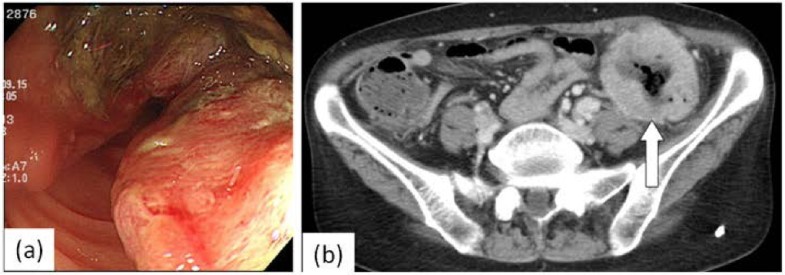

Primary Lung Cancer Presenting With Metastasis To The Colon: A Case

Primary lung cancer presenting with metastasis to the colon: a case wjso.biomedcentral.com

colon cancer lung metastasis primary figure transverse sigmoid presenting case report